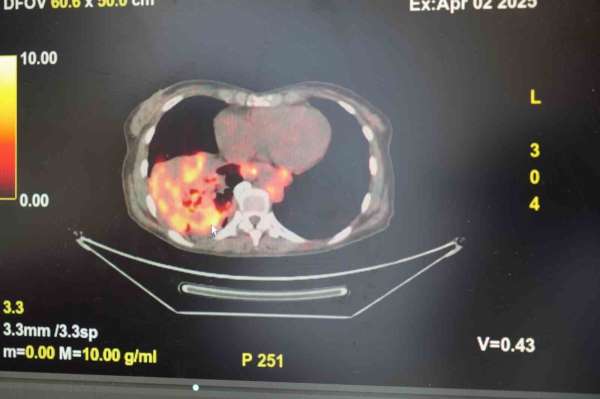

Göğüs Hastalıkları Uzmanı Prof. Dr. Şevket Özkaya, son yıllarda sigara kullanmayan bireylerde de akciğer kanseri vakalarının dikkat çeken bir oranda arttığını belirterek, özellikle kadınlarda görülen adenokarsinom tipi akciğer kanserinin artış gösterdiğine dikkat çekti. Bu konuda yapılan son araştırmalara değinen Özkaya, akciğer kanseri teşhisleri

Dünyanın en prestijli tıp dergilerinden yayımlanan bir araştırma üzerinde açıklama yapan Prof. Dr. Şevket Özkaya, araştırmaya göre, sigara içmeyenlerde en sık görülen tür olan akciğer adenokarsinomu, kadınlarda akciğer kanserlerinin yaklaşık yüzde 60'ını oluşturduğunu söyledi. Prof. Dr. Özkaya, sigara dışındaki risk faktörlerinin başında radon gazının geldiğine dikkat çekerek, 'Radon gazı, evlerimizde farkında olmadan soluduğumuz, renksiz, kokusuz, tatsız ve radyoaktif bir gazdır. Müsaade edilen değerlerin üzerinde solunduğunda akciğer kanseri riskini artırıyor. Radon gazı özellikle taş, toprak ve çimento gibi yapı malzemelerinde doğal olarak bulunuyor. Bu maddelerden ortama sürekli yayılan gaz, solunum yoluyla akciğerlere ulaşıyor' ifadelerini kullandı.